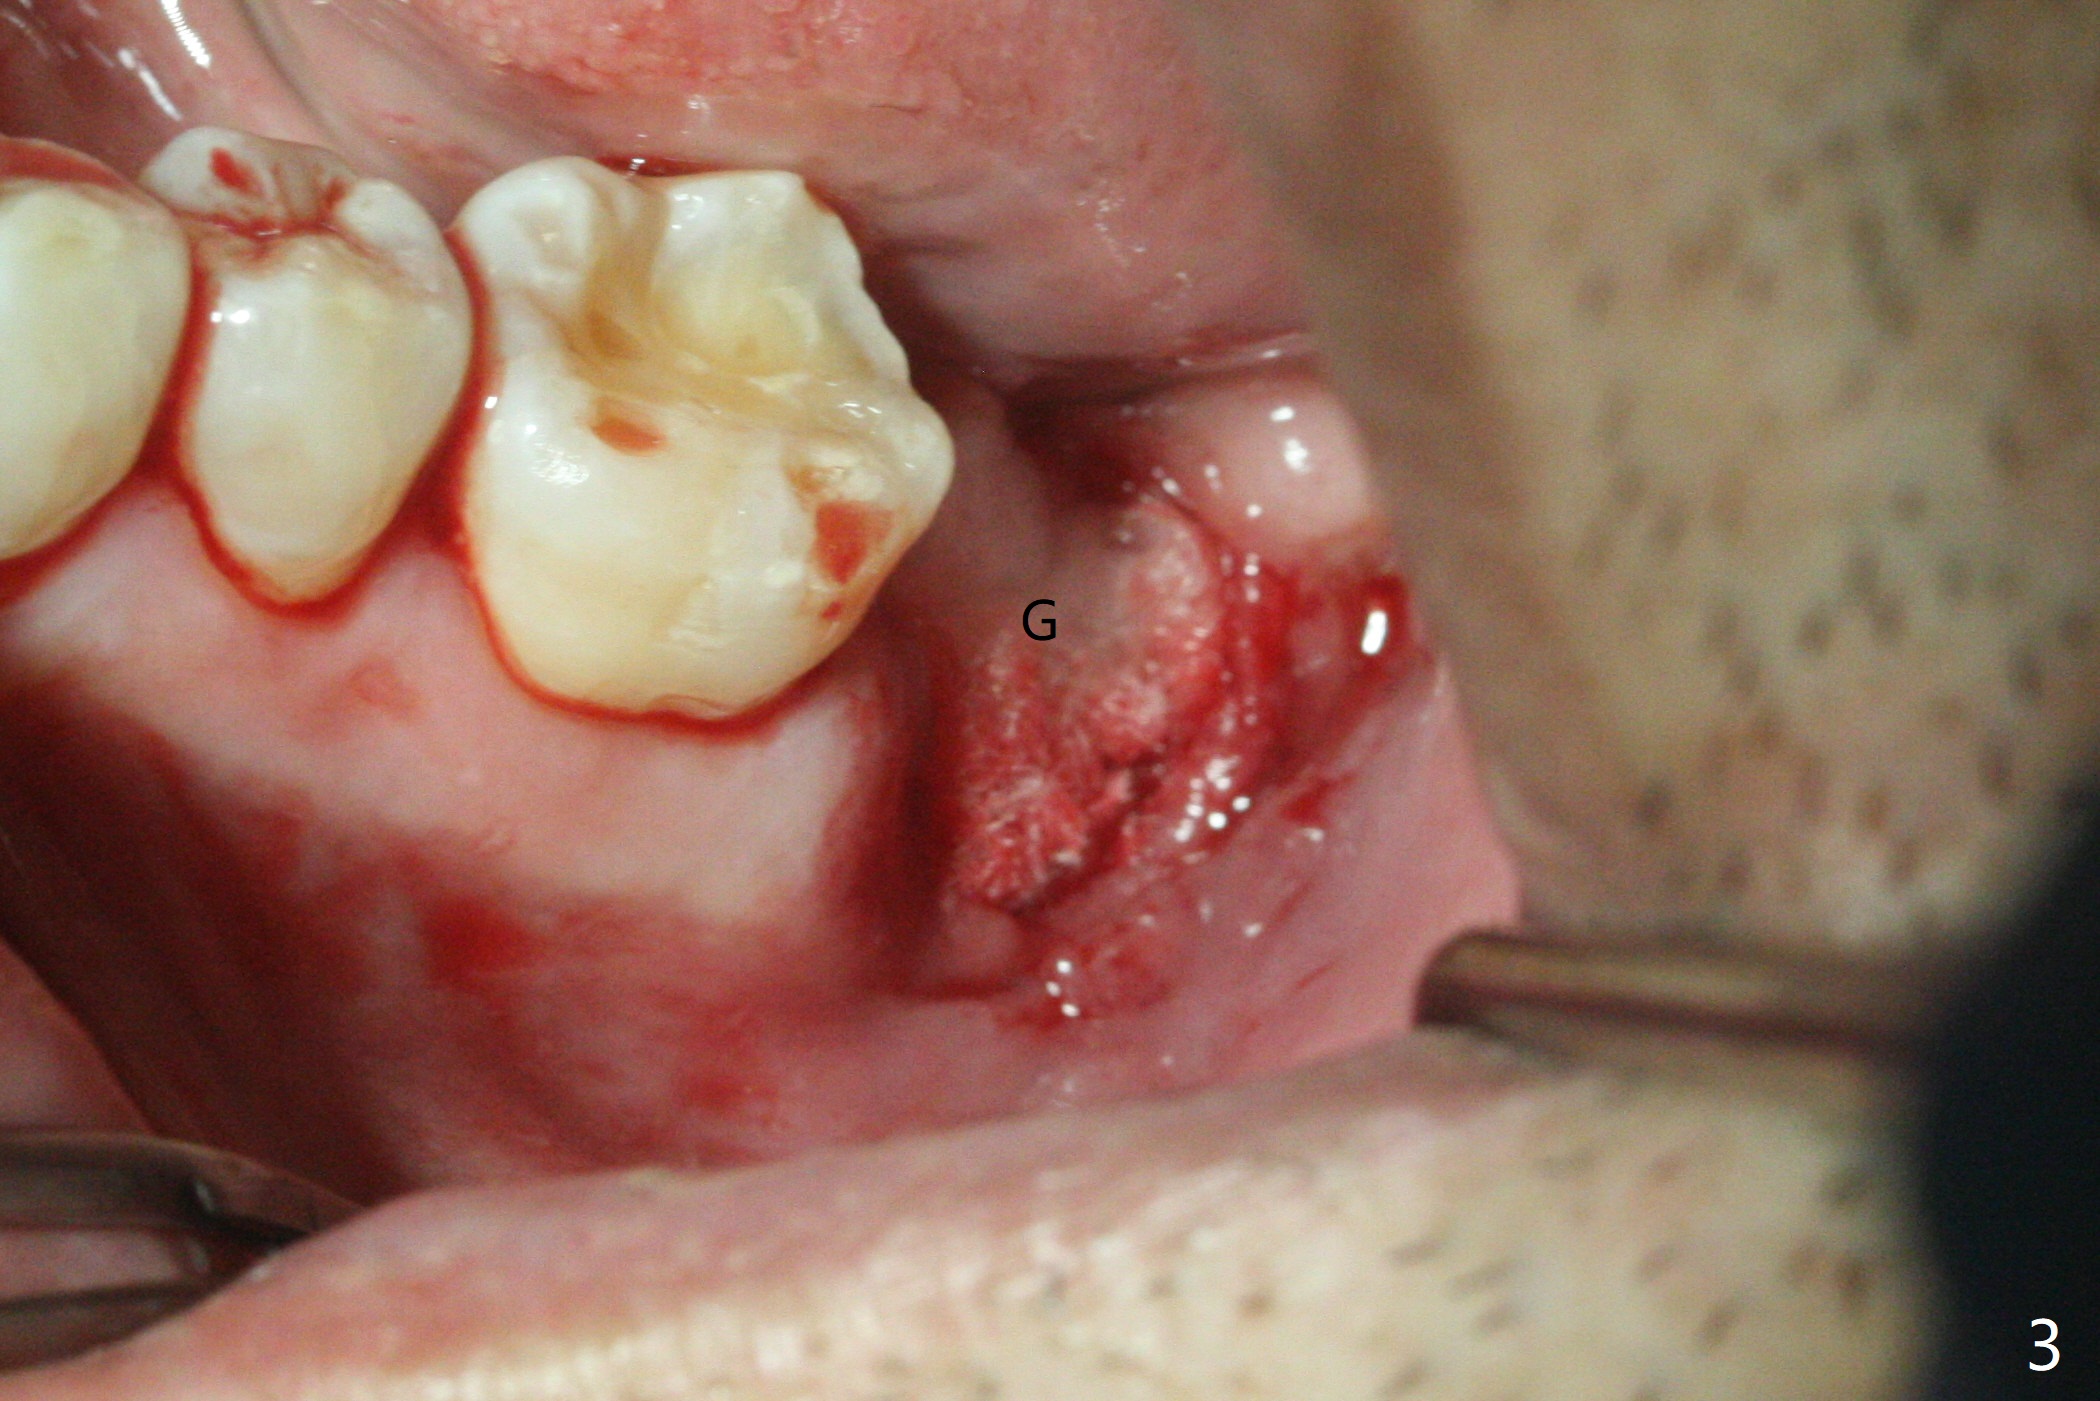

52岁男要求拔除松动左下7(图一,二),同意植骨,我们需要注意什么?我一般在类似情况下,使用浸润麻醉,但是今天改用block anesthesia,加浸润麻醉,直接将局麻药注射于牙龈,疼痛和出血控制好(图三:G(含有肾上腺素纱布)),麻醉方面有什么缺点?我不喜欢block anesthesia,万一碰到神经,麻醉深,病人不会给提醒。牙槽窝近中舌侧远中骨壁肉芽组织彻底清除;由于视野不好,切开(图四),牙槽窝底部*是软的,敢去除吗?其实我第一次向软组织投降,不敢去除,好像挺容易出血,接着敢植骨吗?其实植入粘性骨粉(皮质骨),术后CT检查表明遗留肉芽组织(图五:*),大约4毫米厚(图六),病人身体现在可忙乎了。覆盖PRF膜和不可吸收膜各一张,4-0 PTFE缝合,开口基本关闭,最后使用树脂敷料。